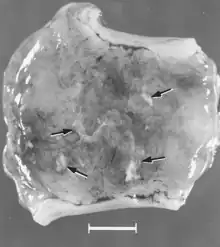

Macroscopic changes of embryos are death followed by resorption of fluids (Fig. 4) and then soft tissues (Fig. 5). Virus and viral antigen are widely distributed in tissues of infected embryos and their placentas,[84] and it is probable that microscopic lesions of necrosis and vascular damage, subsequently described for fetuses, also develop in advanced embryos.

There are numerous macroscopic changes in fetuses infected before they become immunocompetent (Fig. 6). These include a variable degree of stunting and sometimes an obvious loss of condition before other external changes are apparent; occasionally, an increased prominence of blood vessels over the surface of the fetus due to congestion and leakage of blood into contiguous tissues; congestion, edema, and hemorrhage with accumulation of serosanguineous fluids in body cavities; hemorrhagic discoloration becoming progressively darker after death; and dehydration (mummification). Many of these changes also apply to the placenta. Microscopic lesions consist primarily of extensive cellular necrosis in a wide variety of tissues and organs[95][98] (Fig. 7A). Inflammation[98] and intranuclear inclusions[95] also have been described.

Figure 5. Segment of uterus opened to show necrotic remnants of a partially resorbed PPV-infected embryo (arrows) and associated extraembryonic membranes of a gilt experimentally infected oronasally immediately after breeding and killed 22 days later; remnants are laden with virus and viral antigen. Bar = 1 cm.[84]